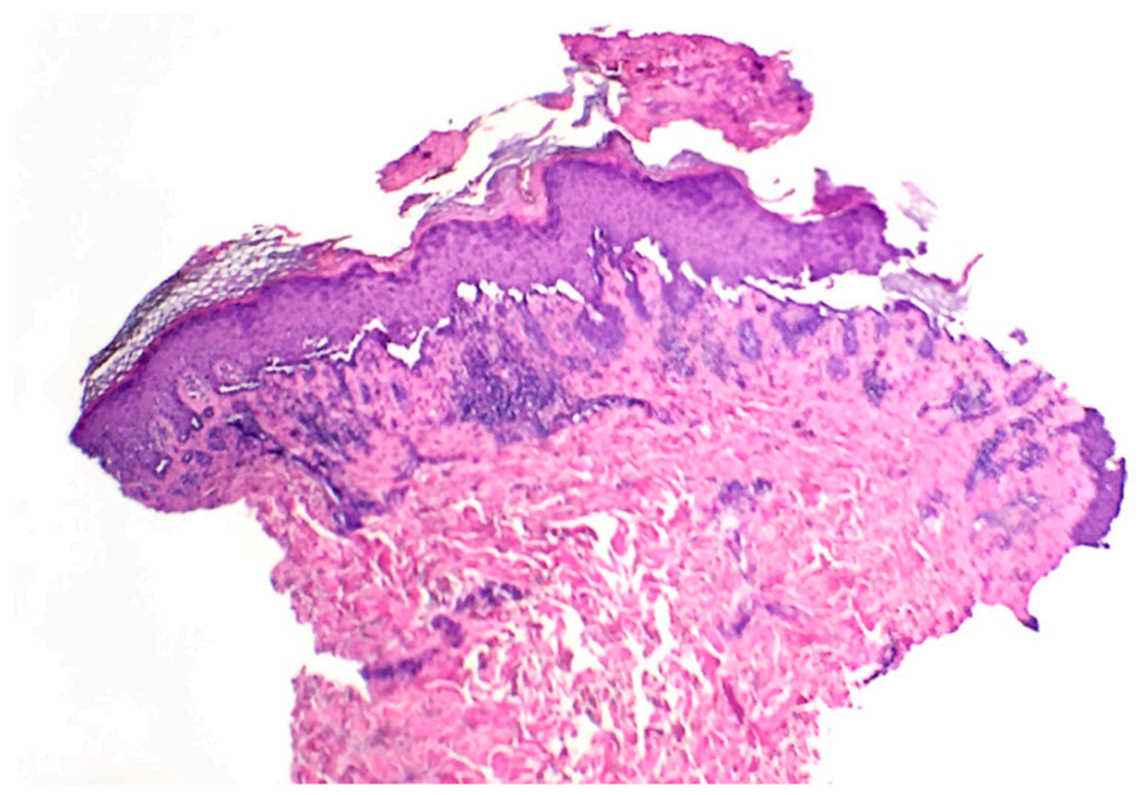

2. Case Report